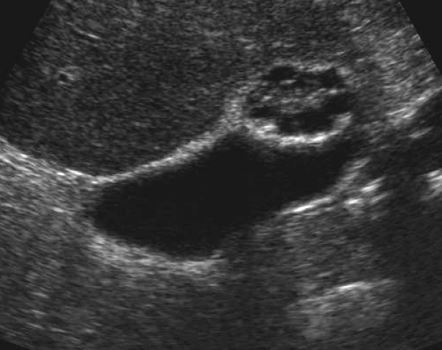

Prominent renal papillary tips

• differential diagnosis of nonshadowing soft tissue masses in the renal calyces

• The normal renal pyramids are cone shaped, with the apex of the cone directed toward the calyx. The rounded

apex, or papillary tip, protrudes into the calyx, producing the typical cuplike appearance seen on intravenous

urograms. However, in the setting of hydronephrosis, the calyx may distend with urine, and the papillary tip can become surrounded by the urine in the calyceal fornices. When viewed in long axis, the morphology of the papillary tip is usually easily visible, and its origin is

recognizable. When viewed in short axis, the papillary tip can simulate a pathologic filling defect in the collecting system. This pitfall is very unusual in native kidneys

and slightly more common in renal transplants.